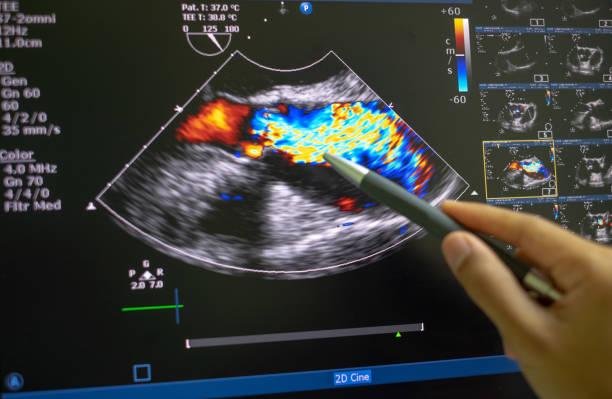

Colour Doppler Ultrasound in Pregnancy

Every expecting parent wants to be assured of the baby’s health during pregnancy. To test concerns and uncertainty of any anomaly in a growing fetus’s health can be resolved by the result of innovative and revolutionary technology. What once seemed unimaginable a few decades ago is now readily available in society. A Colour Doppler Ultrasound...

fetal-echo-test-price

In 2024, Are you looking for a Fetal echo Test? If so, this blog will help you learn all you need to know about Fetal echo scans and how they work. We will also be discussing the Fetal echo test price and fetal echo test in which week is safe? If you’re looking for a...